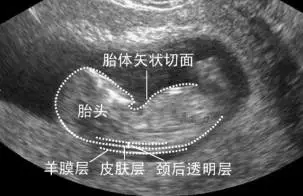

第一:孕10~14周检查,主要测量胎儿颈部透明层厚度(NT),并排除无脑儿等早期即可出现的大畸形。